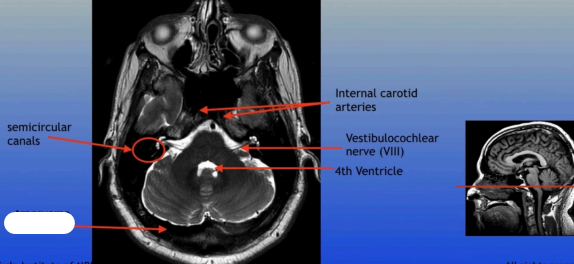

Semicircular Canals

Internal Carotid Arteries

Vestibulocochlear Nerve (VIII)

4th Ventricle